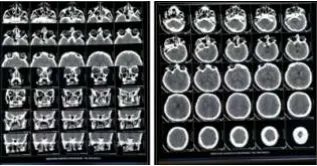

040-68334455Coronavirus disease (COVID-19) is a highly infectious disease leading to fatal morbidity and mortality in patients with severe acute respiratory disease syndrome; pulmonary fibrosis is common with COVID-19. A 32-year-old male with diabetes who was treated for COVID-19 developed left eye proptosis and left facial palsy. Computed tomography brain and orbits were suggestive of mucormycosis.

A 32-year-old diabetic male undergoing treatment for COVID-19 in another hospital, who developed left eye proptosis and left facial palsy was referred to Medicover Hospitals, Chhatrapati sambhaji nagar. Computed tomography (CT)brain and orbit were suggestive of mucormycosis. The patient was referred to a Dentist and the case was operated on with the help of a maxillofacial surgeon.

Functional endoscopic sinus surgery (FESS)and Left subtotal Maxillectomy with left orbital decompression were done, and the sample was sent for histopathological examination. The patient was put on an invasive mechanical ventilator and started on liposomal amphotericin, broad-spectrum antibiotics, and diabetes control. On postoperative day-1 patient developed right-sided hemiplegia. CT brain suggested multiple small infarcts in the thalamus and left parietal region. The patient was treated with antiplatelet and low molecular weight heparin.